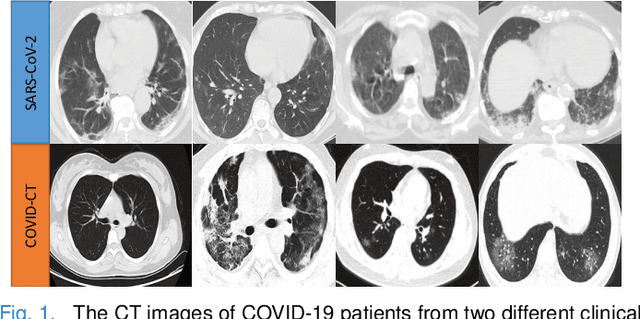

The pandemic of coronavirus disease 2019 (COVID-19) has lead to a global public health crisis spreading hundreds of countries. With the continuous growth of new infections, developing automated tools for COVID-19 identification with CT image is highly desired to assist the clinical diagnosis and reduce the tedious workload of image interpretation. To enlarge the datasets for developing machine learning methods, it is essentially helpful to aggregate the cases from different medical systems for learning robust and generalizable models. This paper proposes a novel joint learning framework to perform accurate COVID-19 identification by effectively learning with heterogeneous datasets with distribution discrepancy. We build a powerful backbone by redesigning the recently proposed COVID-Net in aspects of network architecture and learning strategy to improve the prediction accuracy and learning efficiency. On top of our improved backbone, we further explicitly tackle the cross-site domain shift by conducting separate feature normalization in latent space. Moreover, we propose to use a contrastive training objective to enhance the domain invariance of semantic embeddings for boosting the classification performance on each dataset. We develop and evaluate our method with two public large-scale COVID-19 diagnosis datasets made up of CT images. Extensive experiments show that our approach consistently improves the performances on both datasets, outperforming the original COVID-Net trained on each dataset by 12.16% and 14.23% in AUC respectively, also exceeding existing state-of-the-art multi-site learning methods.